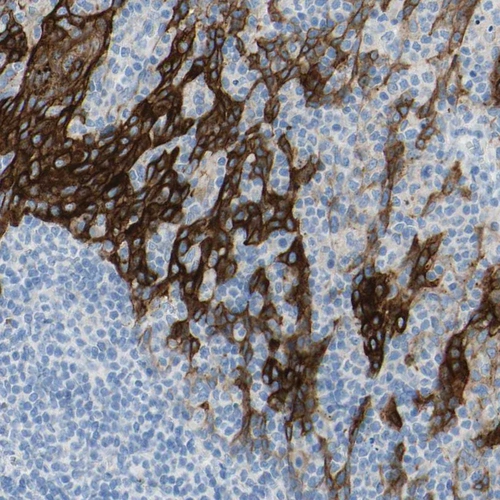

Immunohistochemistry analysis in human esophagus and cerebral cortex tissues using HPA012615 antibody. Corresponding DSC2 RNA-seq data are presented for the same tissues.